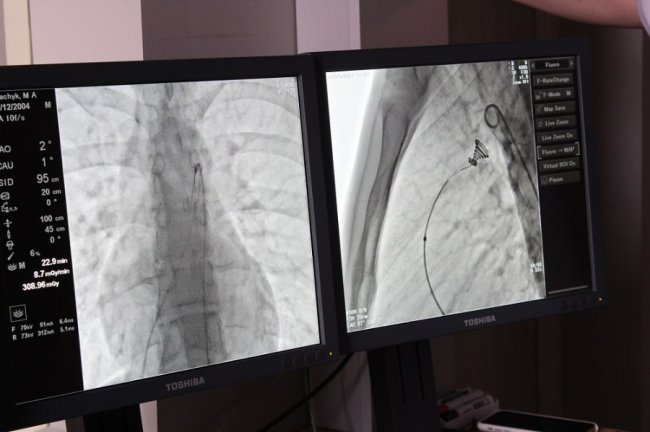

Операція пройшла успішно. Вона була складною. Її проводили під рентгенівським контролем із застосуванням ангіографа, під місцевим знечуленням (без наркозу). Через прокол у стегновій вені і артерії в незакриту протоку встановили оклюдер (маленьку пружинку), яка перекрила потрапляння артеріальної крові у венозне русло.